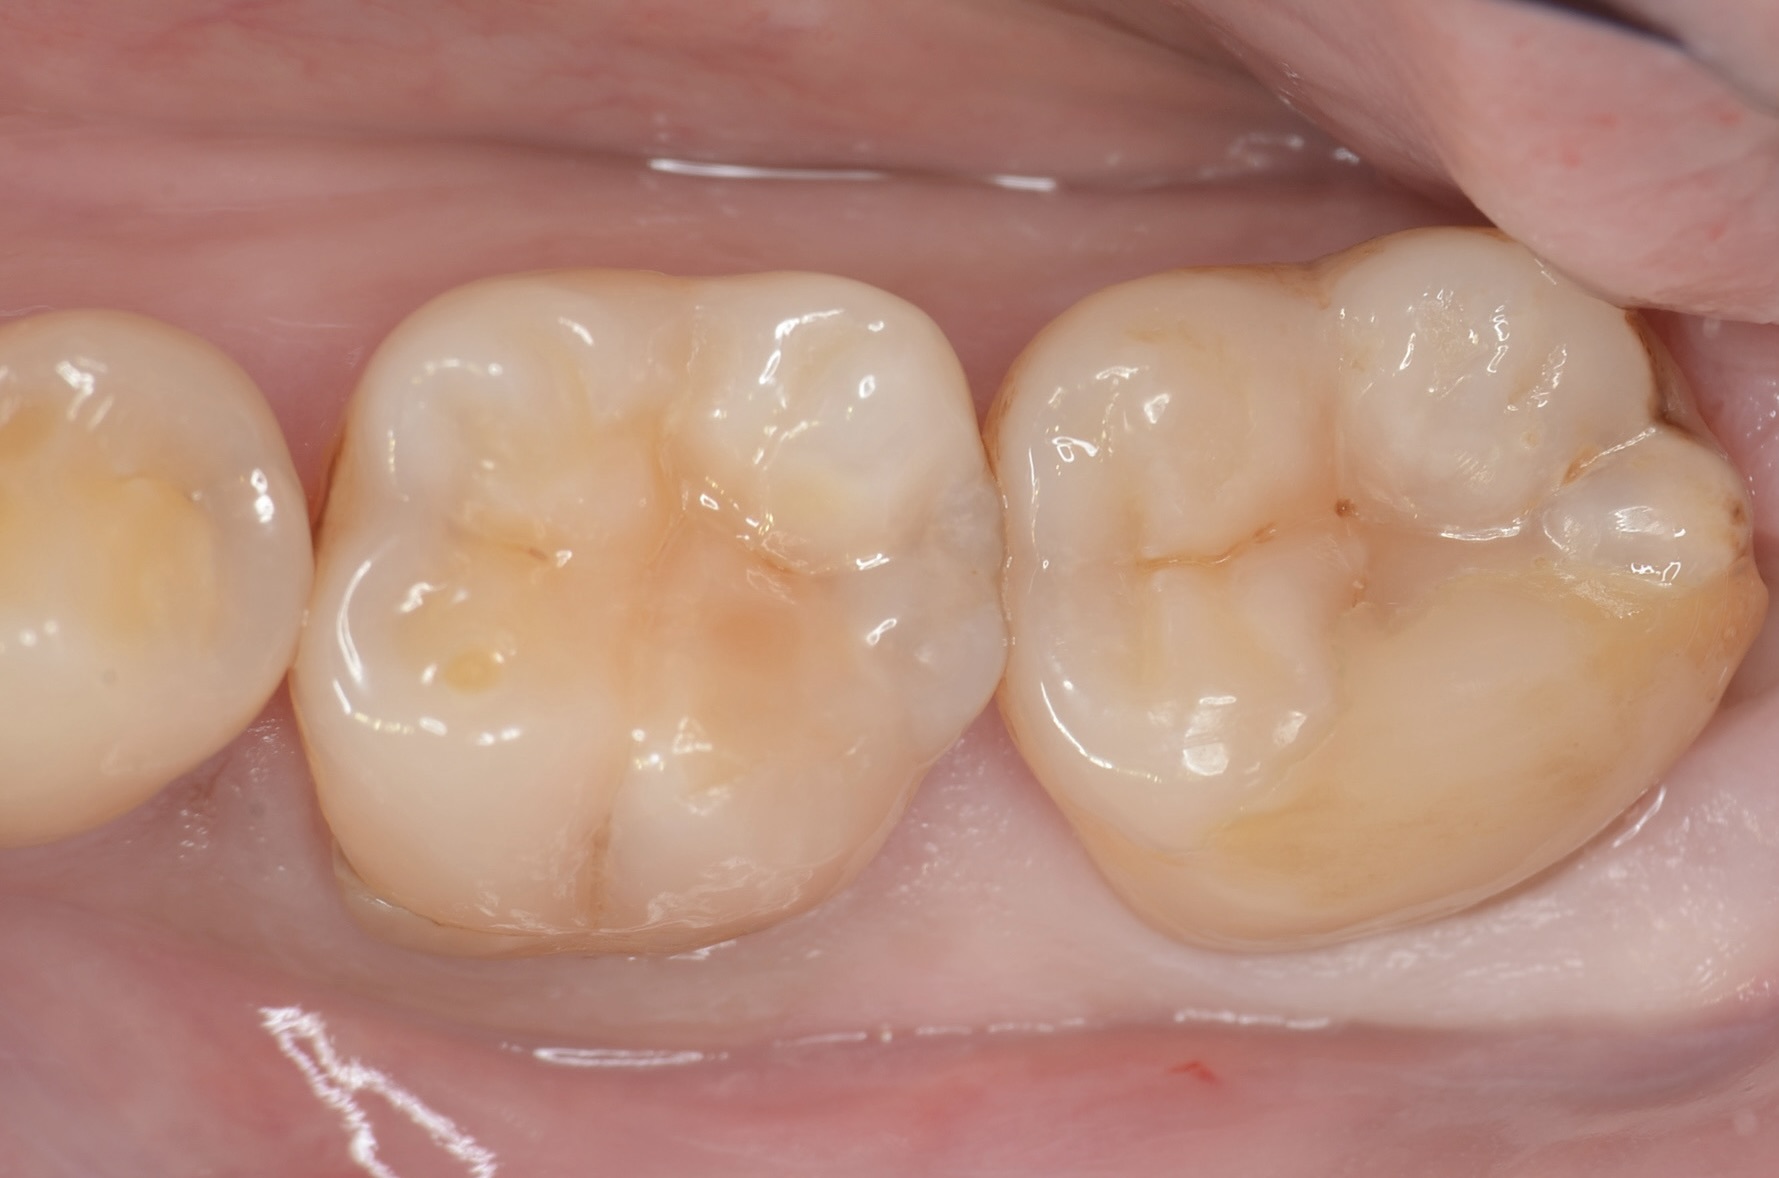

Before

歯垢染め出し

歯垢は接着操作を妨げます。治療前には、必ず歯垢染め出し液により歯垢を見える化し、その後ジェットパウダークリーニングにより徹底的に除去します。保険診療ではここまでする事はほとんどありません。 -